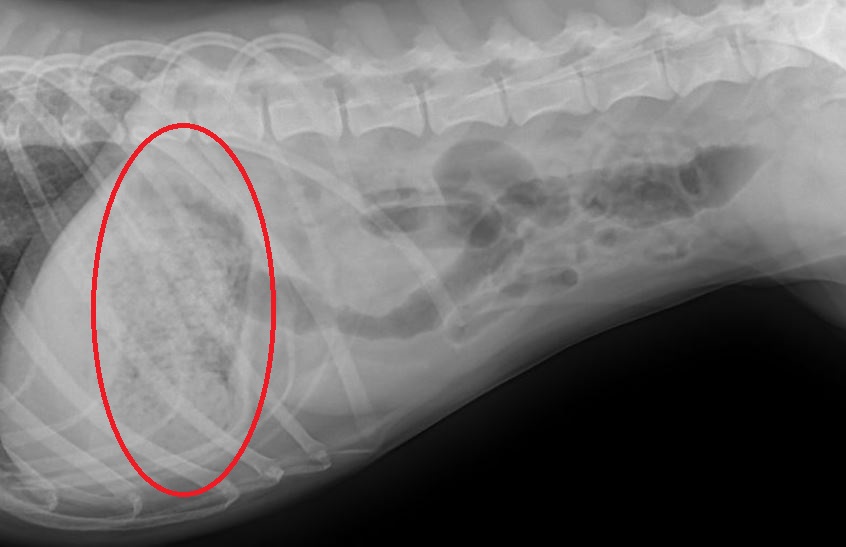

So, as always, my next recommendation was to take an abdominal x-ray to see if anything looked amiss. He had a lot of gas in his colon, and a moderate amount of gas in his small intestine. This could be pancreatitis, colitis, or maybe a foreign body. But, the pattern just didn’t look right for a foreign body obstruction; there usually is not this much gas in the colon. The thing that stood out the most to me was that his stomach was FULL. Full of what if he hadn’t eaten in 7 days?